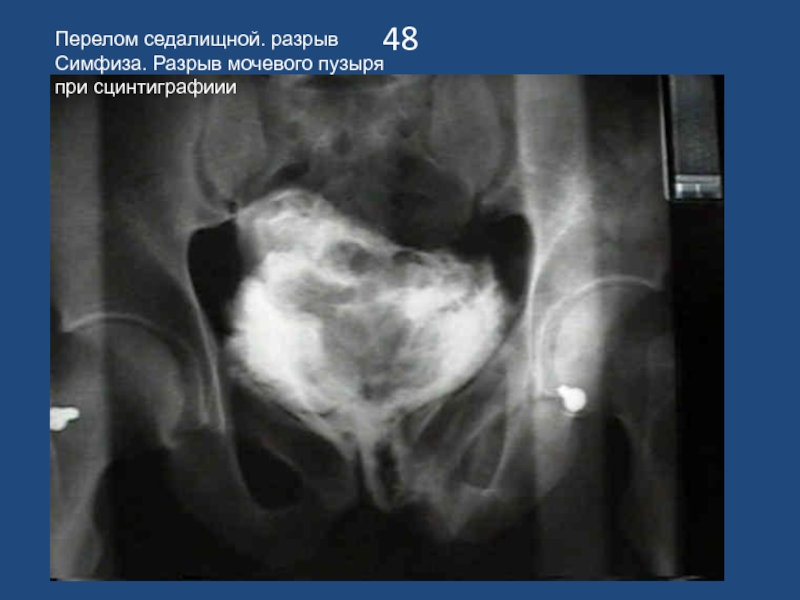

Слайд 4948

Перелом седалищной. разрыв Симфиза. Разрыв мочевого пузыря при сцинтиграфиии

48Перелом седалищной. разрыв Симфиза. Разрыв мочевого пузыря при сцинтиграфиии